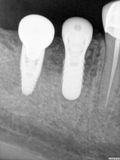

fredlibc | all galleries >> Galleries >> JLin - 46 47 implants > R2.jpg